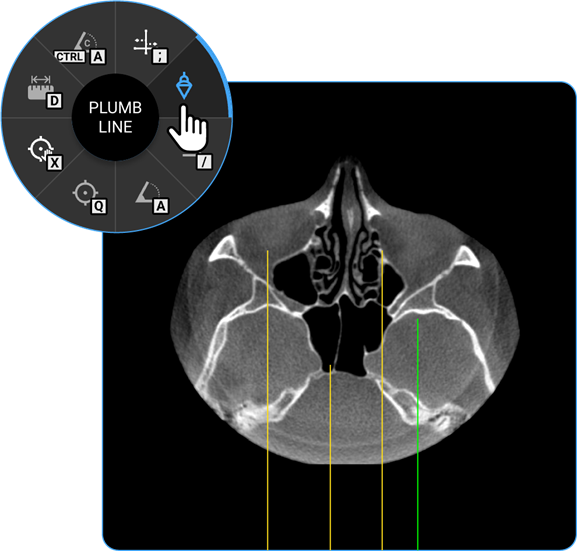

1. Plumb Line: Select the Plumb Line tool to draw a vertical reference line, helpful in assessing alignment or structural deviations.

1. Cobb Angle: Locate the Cobb Angle tool on the adjustment wheel and click on it to measure the degree of spinal curvature, aiding in scoliosis assessment.

1. Length: Locate the Length tool on the wheel and click on it to calculate the distance between two points on the image, useful for measuring anatomical structures.

1. Angle: Click on the Angle tool to determine the angle between two intersecting lines, assisting in anatomical evaluations.

1. Annotate: Use the Annotate tool to add text or markers to the image for documentation or instructional purposes.